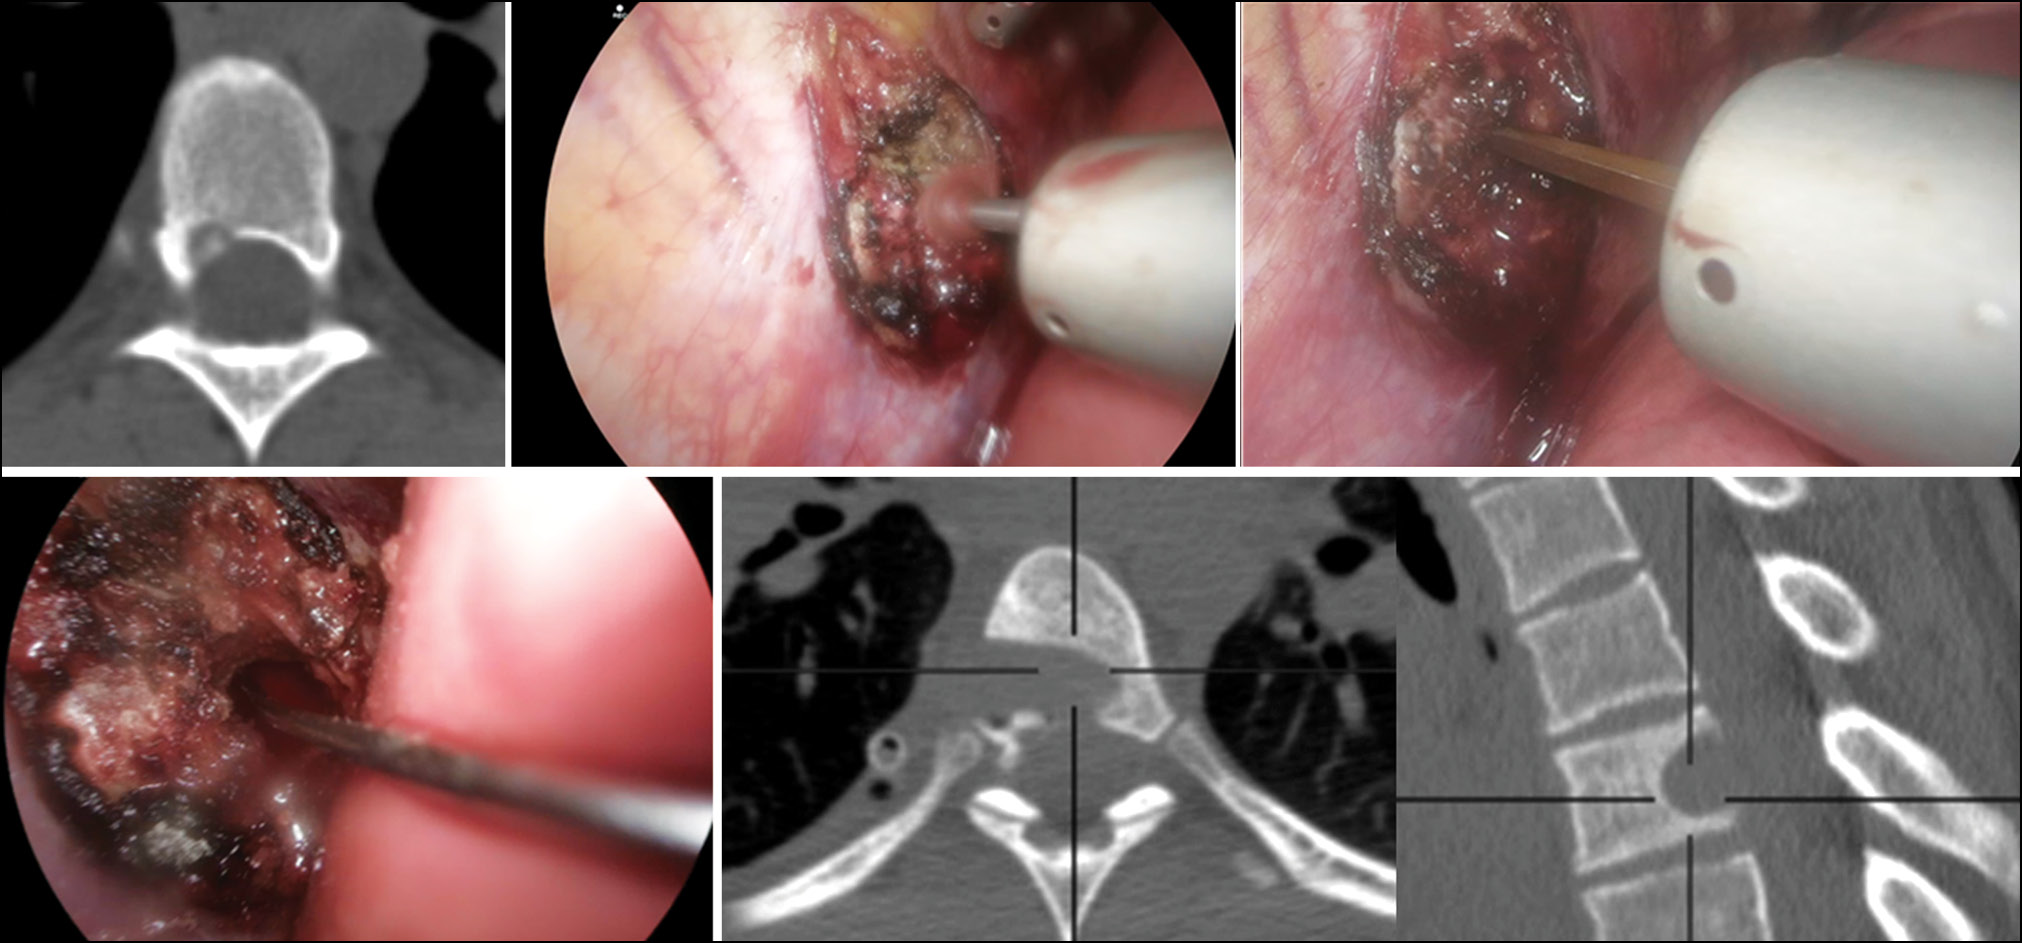

Второй пациент с поражением средней опорной колонны был оперирован в 2023 году. В данном случае наблюдалось поражение на уровне унковертебральной зоны С3 позвонка. В отличие от первого пациента с похожей локализацией опухоли, для проведения хирургического вмешательства был использован доступ по методике Jho [13]. Доступ по Jho успешно применяется при дегенеративно-дистрофических изменениях шейного отдела позвоночника [13]. Тем не менее, по нашим данным, опыта применения этого подхода при опухолевом процессе описано не было. Хирургическое вмешательство проводилось с использованием микроскопа и интраоперационного КТ-контроля (рис. 3).

Рис. 3. Резекция остеоид-остеомы унковертебральной зоны на уровне С3 позвонка с использованием доступа по методике Jho.

Fig. 3. Resection of an osteoid osteoma in the uncovertebral zone at the C3 level using the Jho approach.

Использование данных технологий позволило провести резекцию опухоли локализовано, без потери опороспособности позвонка. Таким образом, мы избежали использования металлофиксации и сохранили подвижность в шейном отделе позвоночника у пациента. В результате выполненного хирургического вмешательства отмечено полное купирование болевого синдрома в шейном отделе, который беспокоил пациента в течение предыдущих двух лет.